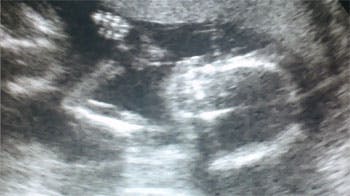

Reality-parret har nu fået kønnet på deres lille guldklump at vide. Se scanningsvideoen her

Katharina er i 18. uge og nu har det glade par fået barnets køn at vide.

Forleden var Katharina, der er i 18-uge, med Peter til scanning på klinikken Lille Københavner, her fik de fastsat terminsdatoen, og fik barnets køn at vide.

Den lille ny vinker til forældrene (Foto: Privat / lillekbher.dk)

- Alt så godt ud, vi skal have en dreng, fortæller den stolte far

Til scanningen optog han en video af den lille ny. Den kan du se herunder: